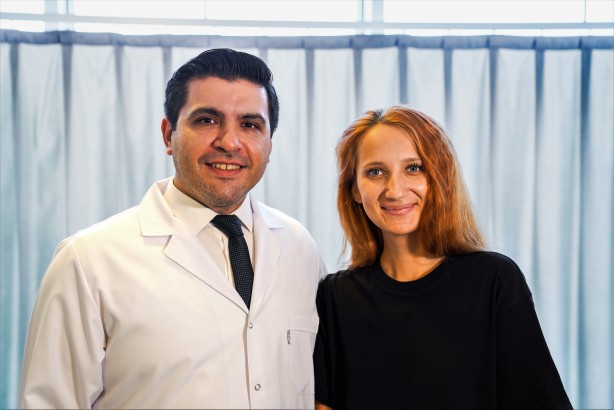

Aynı zamanda omurga eğriliği olarak bilinen skolyozda ameliyat kararını belirleyen faktörlerden birinin ileri derecede eğrilik olduğunu dile getiren Opr. Dr. Uysal, “Omurga eğriliğinin 40 derece ve üzeri olduğu hastalara, ameliyat dışı tedavilerin yeterli olmaması durumunu ve şiddetli ağrıların olup olmadığını da değerlendirerek cerrahi tedavi önermekteyiz. Robotik omurga cerrahisinde kullandığımız yeni nesil MAZOR robotu ile ameliyat öncesi veya ameliyat sırasında, her hastanın omurga yapısına özel olarak planlama yapabilmekteyiz. Buradaki hedefimiz omurlara vida ve rod adını verdiğimiz metal çubuklardan oluşan implantlar yerleştirerek eğriliğin düzeltilmesi ile düzeltilen bölgedeki omurların birbiriyle kaynaşmasını sağlamaktır. Robotik omurga cerrahisinin buradaki inanılmaz etkisi, implantların yerleştirileceği noktaları son derece hassas ve detaylı hesaplamalarla gerçekleştirerek en iyi açının sağlanması ve minimum hata ile ameliyatın tamamlanmasıdır. Ameliyat sırasında yapılan işlemleri eş zamanlı ve en önemlisi 3 boyutlu olarak takip edebiliyor olmamız ise robotik omurga cerrahisinin bizlere sağladığı bir diğer avantajdır” şeklinde ifade etti.